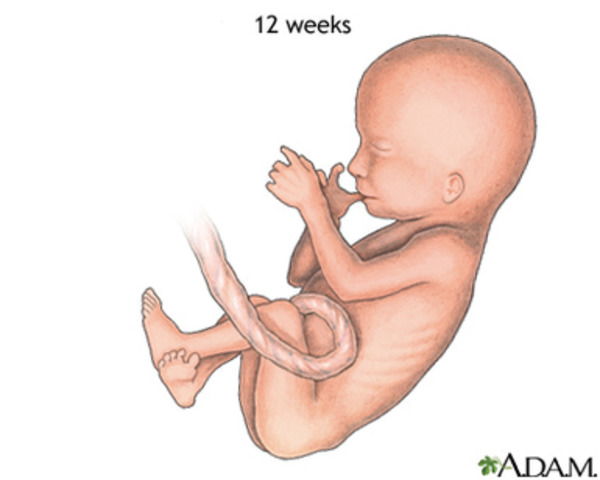

• 12 SEMANA

12 SEMANA

El feto mide 9cm. y pesa entre 15 y 20 gramos. Comienzan a esbozarse las uñas. Aparece en el feto el reflejo de succión. Abre y cierra la boca. Frunce la frente, patea, extiende los dedos de los pies, cierra las manos y puede girar la cabeza. La placenta, que permite la nutrición del feto por medio de nutrientes que le llegan desde la sangre materna, adquiere forma redonda y en su parte central se inserta el cordón umbilical.